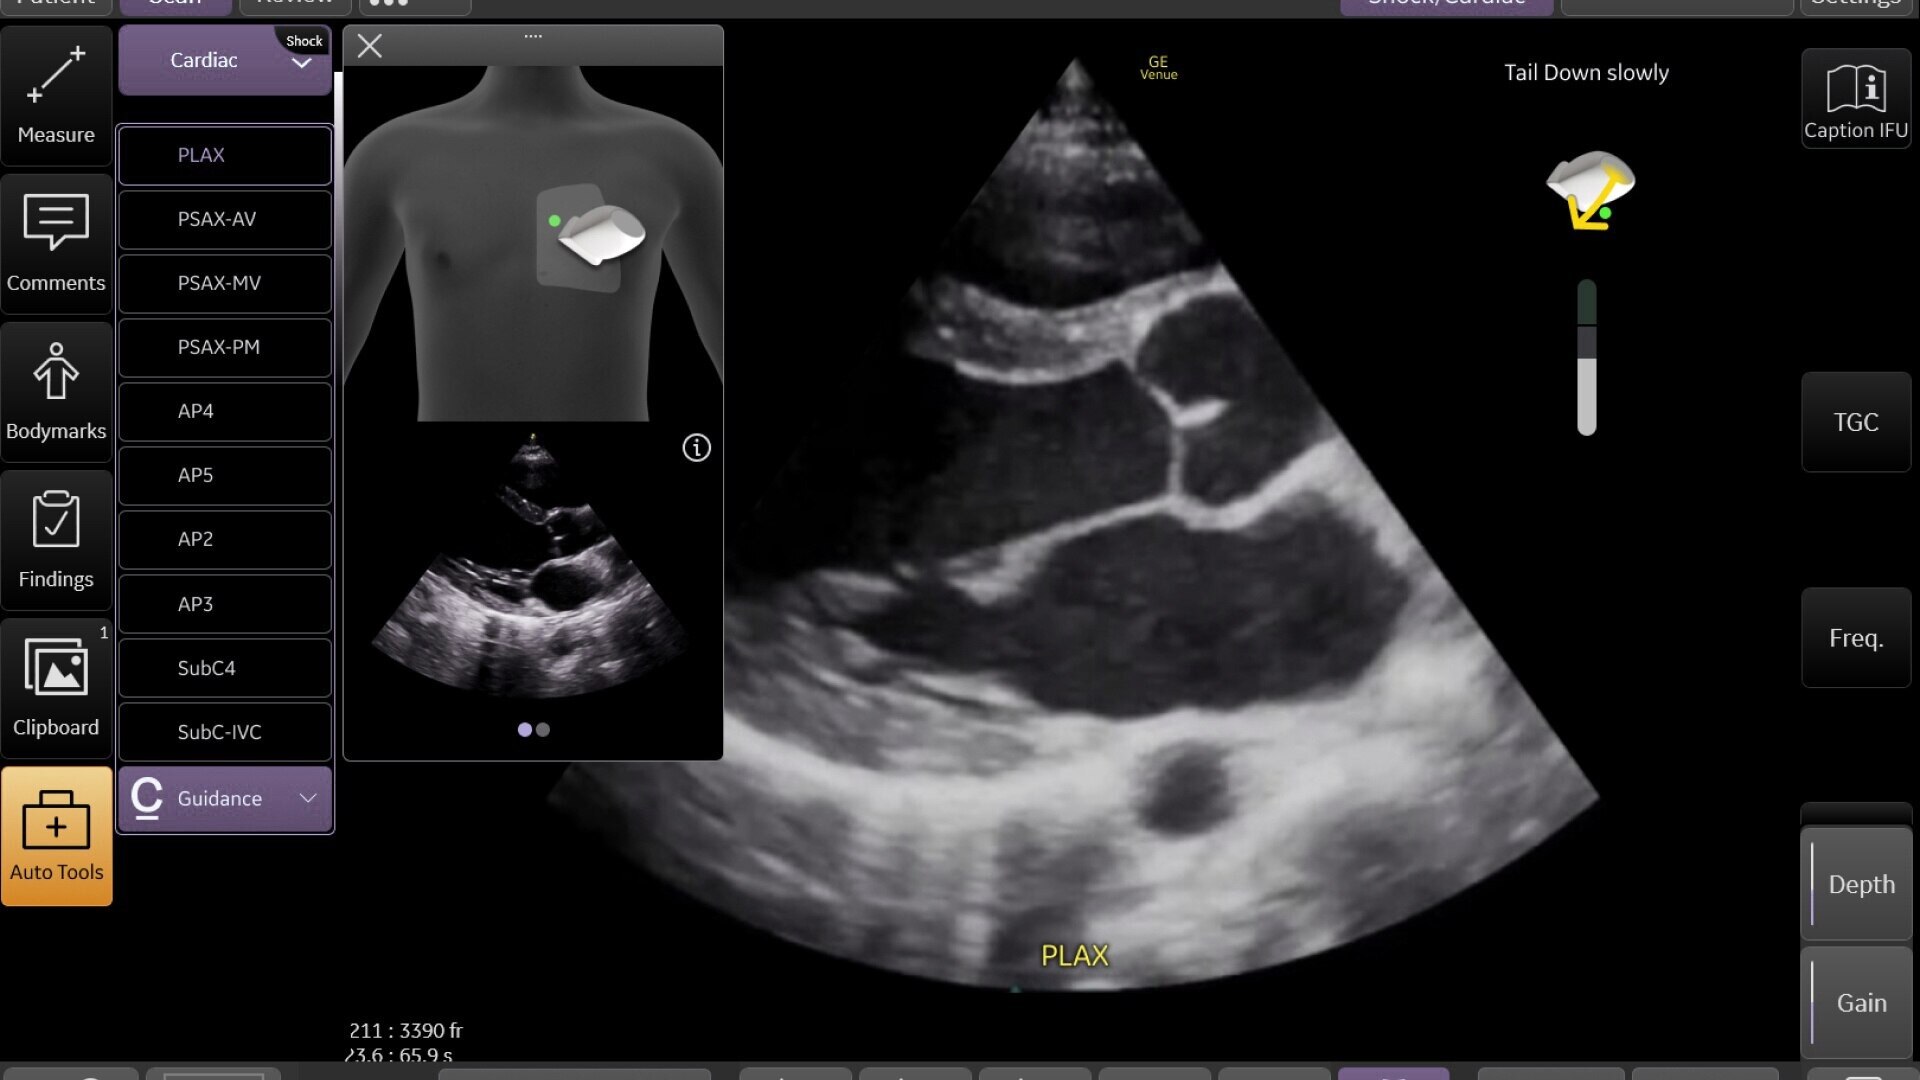

Venue Sprint™ gives you the uncompromised image quality and smart workflow of Venue™ family systems along with the freedom and maximum portability of wireless probes. This all-in-one, entry-level solution combines wireless connectivity with a small, streamlined console. It features Venue family software, to give you access to the AI tools you need, to simplify advanced exams whenever and wherever care is needed.

With the portability and mobility to go anywhere, you can get ahead with Venue Sprint. Take handheld ultrasound to different clinical spaces, sync up and be ready to go. Venue Sprint supports a wide range of environments including:

Critical care

Enables on-the-spot visual confirmation, aiding the team in decision-making and collaboration on complex cases.